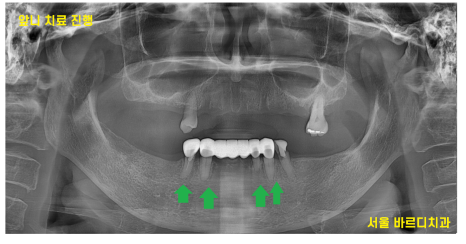

13개의 임플란트 식립 후

전체적인 치아 치료 완료된 사진입니다.

맨 처음 상태가 기억나지 않을 정도이시죠~?

240430

없던 치아가 생겨

씹는 느낌이 새롭다는 환자분 말씀이 기억납니다.